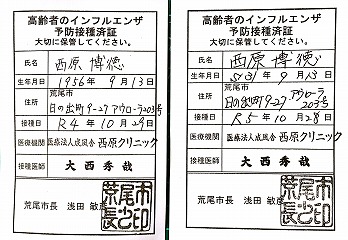

高齢者肺炎球菌予防接種済証.jpg)

高齢者肺炎球菌予防接種済証.jpg)